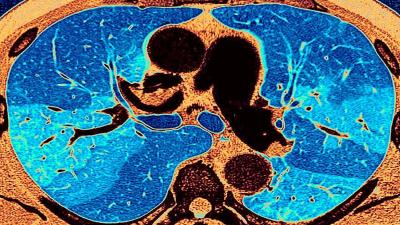

लंग फायब्रोसिस या रोगात फुफ्फुसातील ऊतक म्हणजेच टिश्यू (Tissue) सूजण्यास सुरुवात होते. यामुळे फुफ्फुसांच्या आतल्या हवेची जागा कमी होऊ लागते. याचा परिणाम म्हणजे श्वास घेण्यात अडचण होते. यामुळे एखाद्या व्यक्तीला थकवा जाणवतो. जर परिस्थिती अधिक गंभीर झाली तर रुग्णाचा मृत्यूही होऊ शकतो किंवा त्याला हृदयविकाराचा झटका येऊ शकतो.

याचबरोबर, डॉ. उदवागिया यांनी सांगितले की, काही रुग्णांना बरे झाल्यानंतरही त्यांच्या घरी ऑक्सिजनची आवश्यकता असते. जेव्हा रुग्ण बरे झाल्यानंतर तीन महिन्यांनंतर सीटी स्कॅन केला जातो, तेव्हा त्यांच्या फुफ्फुसांची अवस्था अत्यंत खराब असल्याचे निदर्शनास आले आहे. तीन दशकांपूर्वी लंग फायब्रोसिस रोग सहसा फारच कमी लोकांना होता. ज्यास्तकरून हा रोज वयस्कर लोकांना होता.

फुफ्फुसांची ऊतक सूजलेली आहे. ऑक्सिजनची कमतरता आहे. अशा परिस्थितीत, शरीरात रक्ताचा प्रवाह कमी होऊ लागतो. हृदय योग्यरित्या कार्य करत नाही. याचा परिणाम बहु-अवयव निकामी होणे, हृदयविकाराचा झटका किंवा गंभीर स्थितीत मृत्यू देखील असू शकतो.